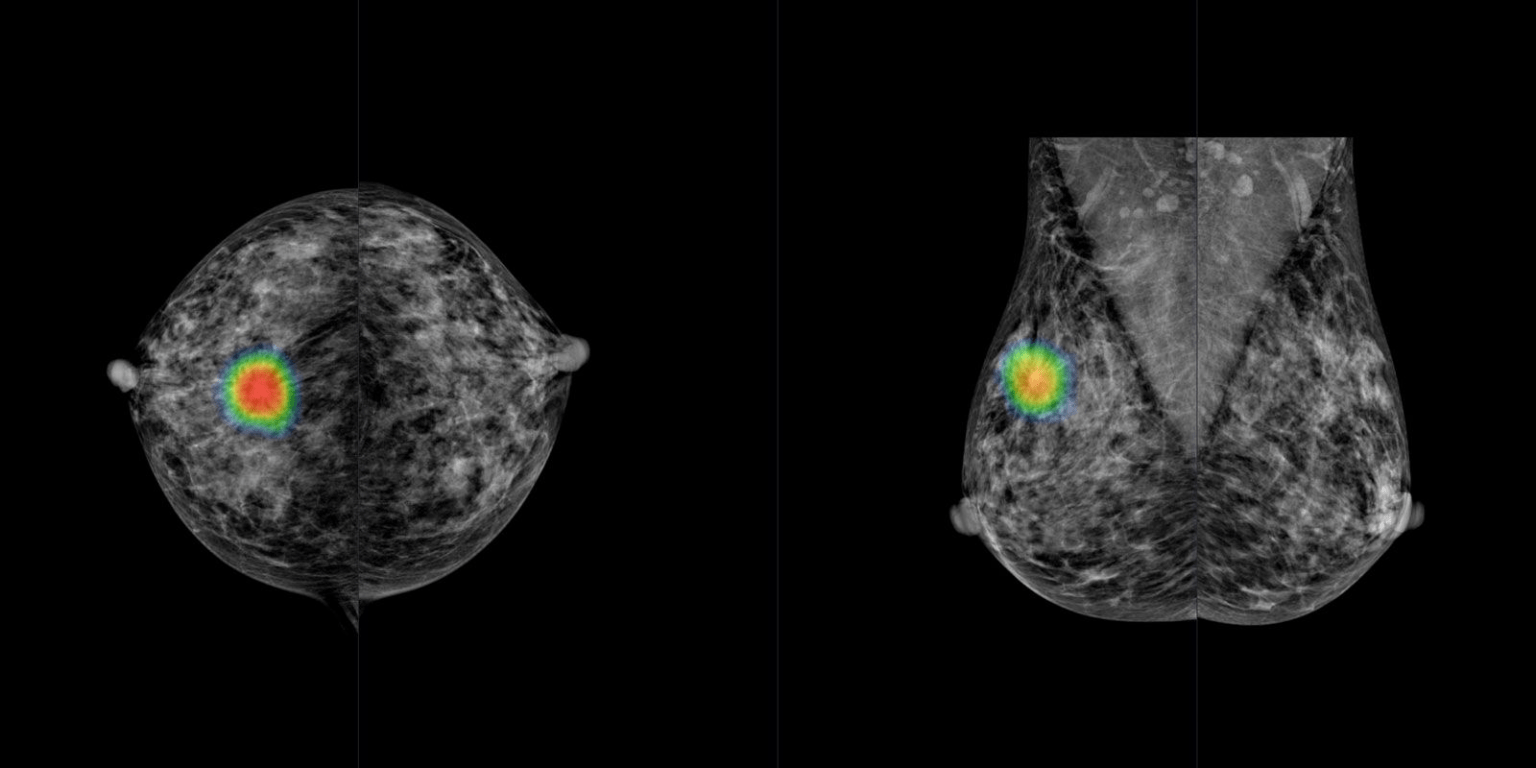

from www.lambertleong.com

Artificial Intelligence Can See Breast Cancer Before it Happens

Artificial Intelligence Can See Breast Cancer Before it Happens Artificial Light And Breast Cancer Artificial lightning has been suggested to be one of the environmental risk factor of breast cancer onset. Exposure to artificial light at night (lan) is commonplace in the developed world. Besides genetic, reproductive, and hormonal factors involved in disease onset and progression, greater attention has focused. When evaluating exposure to lan, both outdoor (e.g., streetlamps, illuminated buildings, lights from vehicles). Artificial Light And Breast Cancer.